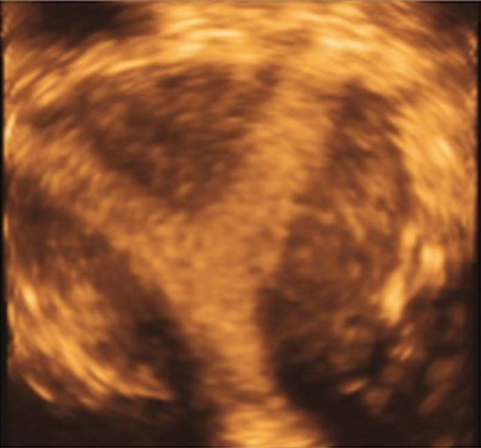

完全纵隔子宫三维超声

不完全纵隔子宫三维超声

一般无症状。临床上主要表现为影响生育期妇女的妊娠结局,包括反复流产、早产、胎膜早破等表现,其中以反复流产为最常见。经阴道超声检查是目前最常用的诊断方法,表现为两个内膜回声区域,子宫底部无明显凹陷切迹。子宫输卵管碘油造影(HSG)有助于了解宫腔形态,评估双侧输卵管通畅与否。宫腹腔镜联合检查是诊断纵隔子宫的“金标准”方法。